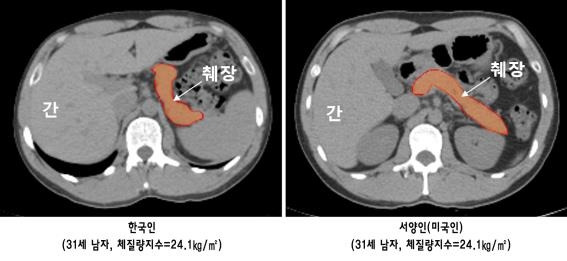

마지막으로 나는 습관적으로 음료수를 마셨다. 넘쳐나는 탄산음료를 대수롭지 않게 마신 것은 미국 이주 초기 내가 한 큰 잘못 중의 하나이다. 미국의 음료수 캔이나 식당에서의 컵 사이즈는 한국에 비해 두 배 정도 또는 그 이상으로 크기 때문에 한국에서의 빈도와 유사하게 음료를 마시더라도 몸에 쌓이는 당분은 배 이상이 되는데 나는 그 결과를 깊이 생각해 보지 않았다. 2018 년경 분당 서울대병원의 연구에 의하면 한국인의 췌장 크기 및 인슐린 분비능은 서양인에 비해 적어 같은 조건이라도 당뇨병에 더욱 취약할 수 있는데 나는 이러한 건강/의학적 지식에 무지한 채 많은 미국 사람들의 습관과 같이 물처럼 음료수를 마셔댔던 것이다. 이 외에도 스트레스 해소를 위해 저녁마다 맥주를 마셨고 알코올이 근육을 분해하면서 내 몸은 더욱 더 지방형 체형으로 바뀌어 갔다. 스트레스와 음주가 계속되니 피로가 가실 일이 없어 커피 역시 자주 마셨고, 뇌를 인위적으로 각성시키는 카페인에 더욱 의존하며 불면증이 심화되었다.

(한국인과 서양인의 췌장 크기 비교, 이미지 출처: https://www.yna.co.kr/view/AKR20180727127900017)